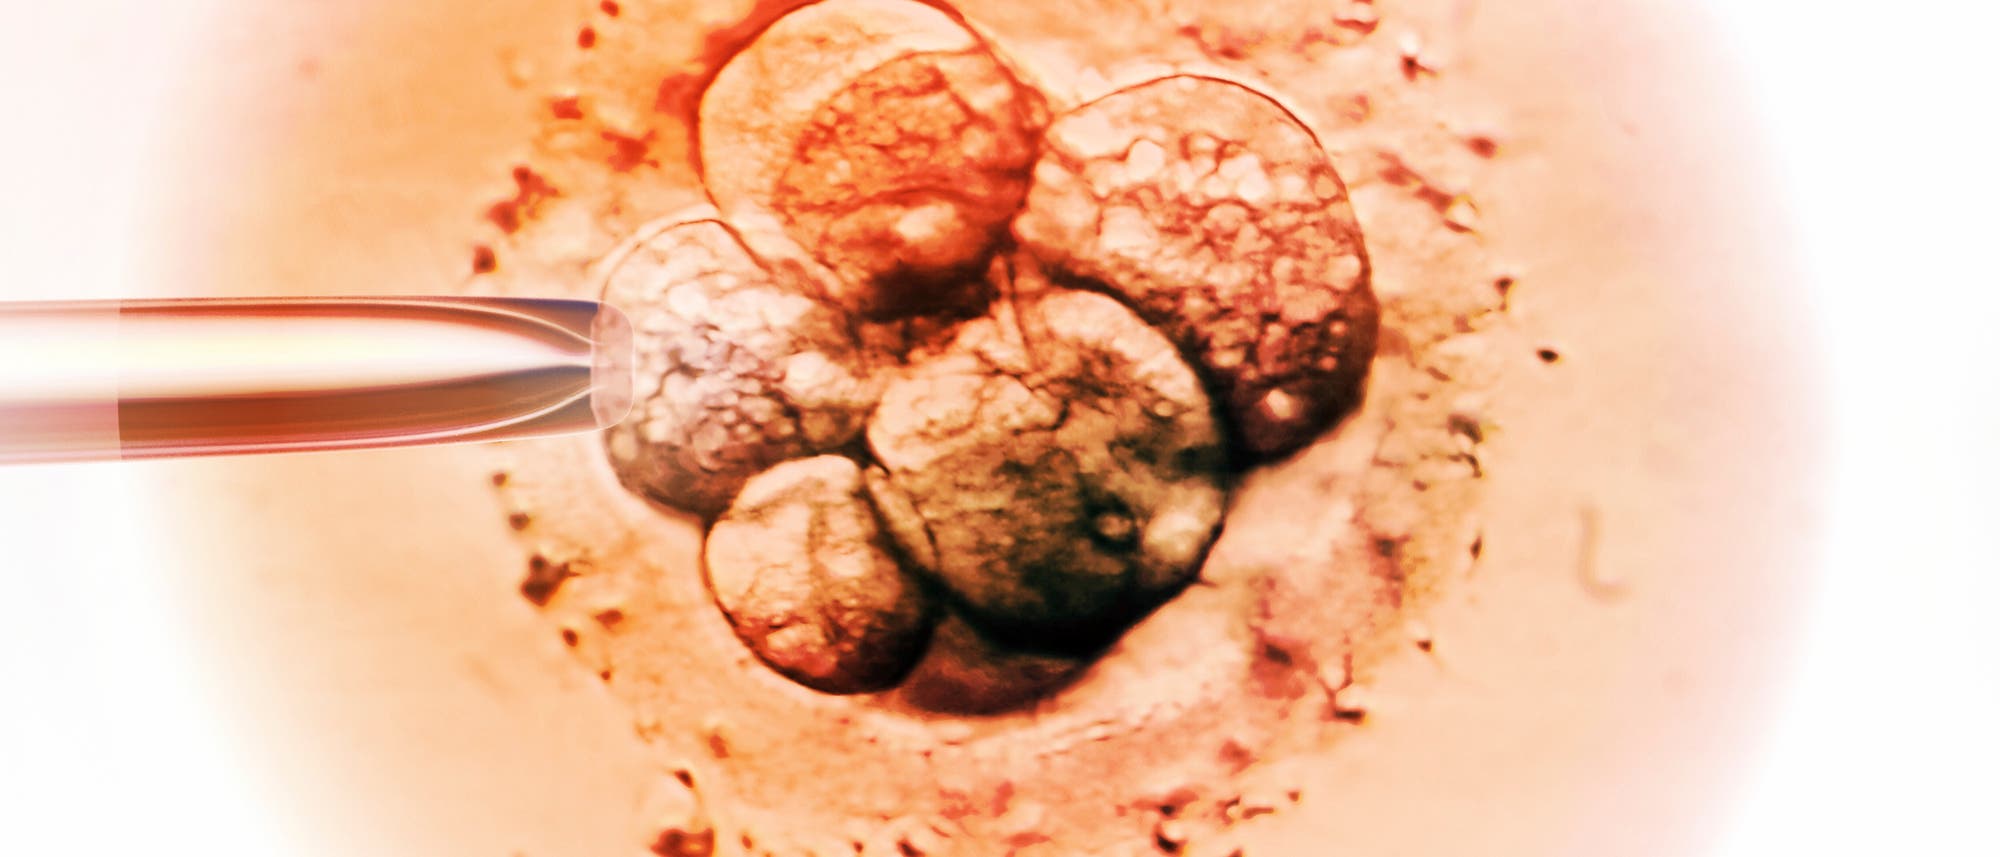

Am 25. Juli 1978 vermelden der Gynäkologe Patrick Steptoe, der Embryologe Robert Edwards und die Embryologin Jean Purdy in Oldham, England, eine Sensation: die Geburt von Louise Brown. Dem weltweit ersten Baby, bei dem die Befruchtung außerhalb des menschlichen Körpers stattfand, »in vitro« (was oft mit »im Reagenzglas« übersetzt wird, obwohl der entscheidende Schritt in einer Petrischale passiert). Die Wissenschaftler hatten der Mutter eine Eizelle entnommen, sie im Labor mit dem Sperma des Vaters befruchtet und dann in die Gebärmutter eingesetzt – der Beginn der In-vitro-Fertilisation (IVF).

Weitere Durchbrüche folgten: 1992 wurden erstmals Ei- und Spermienzelle in der Petrischale von Menschenhand zusammengeführt – die Intrazytoplasmatische Spermieninjektion (ICSI) kommt insbesondere bei männlicher Unfruchtbarkeit zum Einsatz. In den 1990er-Jahren wurde es auch möglich, Embryonen vor der Implantation genetisch zu untersuchen – die Präimplantationsdiagnostik (PID) darf in Deutschland unter strengen Auflagen zur Vermeidung schwerer genetischer Erkrankungen eingesetzt werden. Ab den 2010er-Jahren konnten Eizellen auch zu nichtmedizinischen Zwecken eingefroren werden, was Frauen neue Möglichkeiten der Familienplanung bot.

»Wir führen weiter, was Robert Edwards begonnen hat«, sagt die Frau auf dem Bildschirm. Stephanie Kuku schaltet sich für das Gespräch aus ihrem Wohnzimmer in London zu. Die 45-Jährige pendelt zwischen der englischen Hauptstadt und New York, wo ihr Arbeitgeber sitzt: das Start-up Conceivable Life Sciences. Kuku ist dessen Chief Knowledge Officer und erklärt die Idee: eine Maschine zur künstlichen Befruchtung. Man gibt Eizellen und Spermien hinein, dann führt die Maschine die weiteren Schritte automatisch durch: die Auswahl der Zellen, die Befruchtung, das Überführen der befruchteten Eizelle in ein Nährmedium, wo sie sich teilt. Eine künstliche Intelligenz trifft die Entscheidungen, Roboterarme, wie sie in der Halbleiterindustrie verwendet werden, führen die Arbeitsschritte aus. Anfangs überwacht von Experten, später ganz allein, so ist die Idee. Im April wurde in einer Kinderwunschklinik in Mexiko zum ersten Mal ein Kind geboren, bei dem die Ei- und Spermienzelle seiner Eltern vollautomatisiert durch das Conceivable-System zusammengeführt wurden.